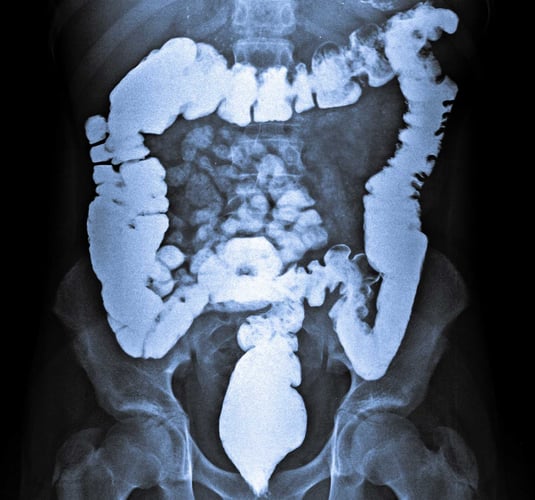

Alt vi spiser og drikker, glir ned i magesekken. Der blandes det med magesyre, og så sendes det videre gjennom tarmen. Tarmen ligger som en lang, krøllete pølse inni oss. I tarmen blir maten knadd og blandet sånn at kroppen kan suge til seg det den har bruk for.

Tarmen er mange meter lang, og den har utrolig mange nerver i forhold til andre organer i kroppen. Det er bare ett annet organ som har like mange nerver, nemlig hjernen. Forskere har undersøkt hvordan nervene i tarmen reagerer på tarmbakteriene, og hvordan det igjen påvirker humøret vårt.